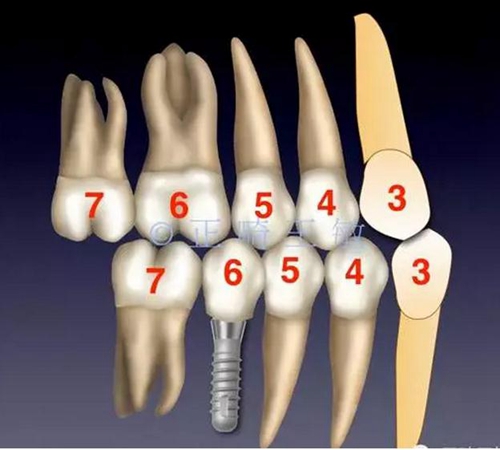

前幾天寫了篇正畸輔助種植治療的文章,簡(jiǎn)單介紹了種植間隙不足,正畸如何配合治療。幾天來(lái),好評(píng)如潮,很高興能和各位老師如此便捷的討論。今天接著寫一篇續(xù)集,如果缺牙的同時(shí),又伴有牙齒排列的問(wèn)題,該如何設(shè)計(jì)方案。

首先來(lái)看這樣一個(gè)病例:

這樣的情況看起來(lái)很復(fù)雜,缺2個(gè)牙,三類關(guān)系,擁擠,又偏又反。如何處理?